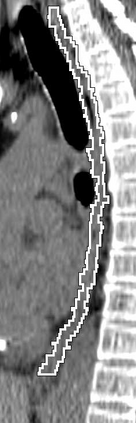

Stereotactic body radiation therapy allows for a precise and accurate dose delivery. Organ motion during treatment bears the risk of undetected high dose healthy tissue exposure. An organ very susceptible to high dose is the oesophagus. Its low contrast on CT and the oblong shape renders motion estimation difficult. We tackle this issue by modern algorithms to measure the oesophageal motion voxel-wise and to estimate motion related dosimetric impact. Oesophageal motion was measured using deformable image registration and 4DCT of 11 internal and 5 public datasets. Current clinical practice of contouring the organ on 3DCT was compared to timely resolved 4DCT contours. The dosimetric impact of the motion was estimated by analysing the trajectory of each voxel in the 4D dose distribution. Finally an organ motion model was built, allowing for easier patient-wise comparisons. Motion analysis showed mean absolute maximal motion amplitudes of 4.24 +/- 2.71 mm left-right, 4.81 +/- 2.58 mm anterior-posterior and 10.21 +/- 5.13 mm superior-inferior. Motion between the cohorts differed significantly. In around 50 % of the cases the dosimetric passing criteria was violated. Contours created on 3DCT did not cover 14 % of the organ for 50 % of the respiratory cycle and the 3D contour is around 38 % smaller than the union of all 4D contours. The motion model revealed that the maximal motion is not limited to the lower part of the organ. Our results showed motion amplitudes higher than most reported values in the literature and that motion is very heterogeneous across patients. Therefore, individual motion information should be considered in contouring and planning.